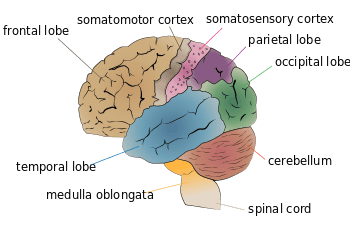

The frontal lobe, located at the front of the brain, is one of the four major lobes of the cerebral cortex in the mammalian brain. The frontal lobe is located at the front of each cerebral hemisphere and positioned in front of the parietal lobe and above and in front of the temporal lobe. It is separated from the parietal lobe by a space between tissues called the central sulcus, and from the temporal lobe by a deep fold called the lateral sulcus also called the Sylvian fissure. The precentral gyrus, forming the posterior border of the frontal lobe, contains the primary motor cortex, which controls voluntary movements of specific body parts.

On the lateral surface of the human brain, the central sulcus separates the frontal lobe from the parietal lobe. The lateral sulcus separates the frontal lobe from the temporal lobe.

Left frontal lobe (click to view animation) Lobes

Base of brain. Human brain showing the four major lobes of the cerebrum. Beneath the cerebral cortex are the cerebellum, pons, olive, and medulla oblongata